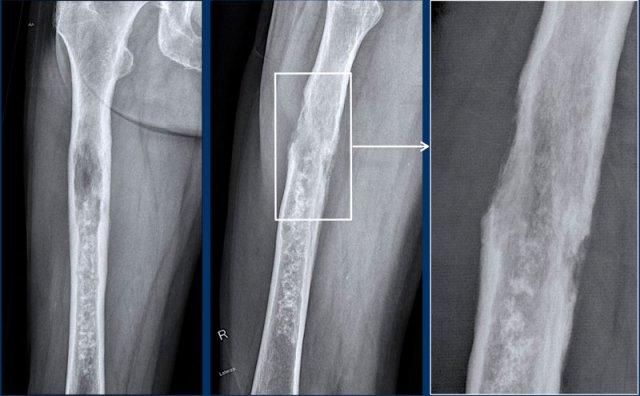

Đầu tiên hãy xem các hình ảnh của bệnh nhân 79 tuổi bị u xương.

Sau đó tiếp tục đọc.

Hình ảnh

Phim X-quang cho thấy một khối u lớn ở thân xương đùi với hình ảnh vôi hóa dạng bỏng ngô điển hình ở phần xa và thành phần tiêu xương nhiều hơn ở phần gần.

Hình ảnh phóng đại chi tiết ở tư thế nghiêng cho thấy khối u xâm lấn vỏ xương và nguy cơ cao gãy xương bệnh lý.

Phần đuôi của khối u có hình ảnh giống u sụn không điển hình (ACT) với hiện tượng lõm vỏ xương khu trú, trong khi phần đầu có hình ảnh giống u sụn ác tính độ cao (CS độ cao).

Kết luận

Đây là hình ảnh điển hình của sarcoma sụn phản biệt hóa, với một phần có biểu hiện như khối u sụn độ thấp đến trung bình với sự chuyển tiếp đột ngột sang thành phần sarcoma độ cao (đôi khi không có nguồn gốc sụn).

Phân nhóm này

thường gặp ở người lớn tuổi.

Tỷ lệ sống còn toàn bộ của sarcoma sụn phân hóa kém rất thấp so với sarcoma sụn độ II và độ III, do bệnh nhân thường đã có di căn phổi và xương tại thời điểm chẩn đoán.

Lưu ý khuyết tật vỏ xương trên ảnh T2 DIXON axial và khối mô mềm xung quanh.

Một phần khối u không ngấm thuốc và vùng chất nhầy này cho thấy đây là u sụn ác tính độ cao.

Như trên phim X-quang, trường hợp này là một chondrosarcoma phân hóa kém điển hình, trong đó phần dưới có biểu hiện như một ACT và phần gần như một sarcoma độ cao.

Thường gặp dưới dạng khối u lớn ở bệnh nhân cao tuổi.

Hình ảnh tưới máu cho thấy

sự tăng cường tín hiệu không đồng nhất trong khối u sụn biệt hóa kém này.

Phần nhầy (đường màu xanh lam)

không có sự tăng cường tín hiệu.

Chúng tôi đã thảo luận trước đây rằng 18F-FDG PET-CT không được khuyến cáo cho u sụn ác tính để phân biệt giữa khối u sụn không điển hình và các khối u độ cao.

Tuy nhiên, trong ung thư sụn dạng biệt hóa,

PET CT kết hợp với CT chẩn đoán lồng ngực có thể được thực hiện để tìm kiếm bệnh di căn.

Ung thư sụn dạng biệt hóa ở xương đùi phải cho thấy độ bắt giữ FDG cao và hình ảnh toàn thân cho thấy nhiều di căn xương ở xương đùi trái, xương đòn trái, các xương sườn trên bên phải và xương ức.

Di căn hạch bạch huyết cạnh chậu hiện diện ở cả hai bên.

Do chondrosarcoma không nhạy cảm với xạ trị và hóa trị, bệnh nhân được điều trị giảm nhẹ, bao gồm đóng đinh xương đùi phải để phòng ngừa gãy xương.

Thật không may, bệnh nhân đã phát triển gãy xương bệnh lý ở xương đùi trái và sau đó đã được điều trị.

Hình ảnh CT ngực theo mặt phẳng coronal cho thấy khối mô mềm xung quanh

ổ di căn tại xương đòn trái.

Không phát hiện di căn phổi.

Tiên lượng của u sụn dạng biệt hóa kém rất xấu với tỷ lệ sống còn toàn bộ 5 năm khoảng 18%.